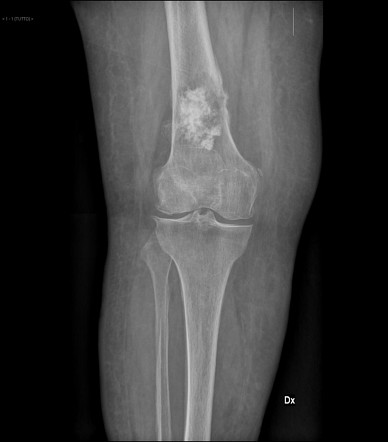

- Osteochondroma

- Patho/Etiology: Most common benign bone tumor, characterized by a cartilage-capped bony projection arising from the external surface of a bone. It’s an outgrowth of the growth plate.

- Clinical Presentation: Most common in males < 25 years old. Usually found incidentally or as a painless mass near the metaphysis of long bones, especially the knee.

- Dx: X-ray shows a pedunculated or sessile growth pointing away from the joint.

- Key Associations: Can rarely transform into chondrosarcoma.